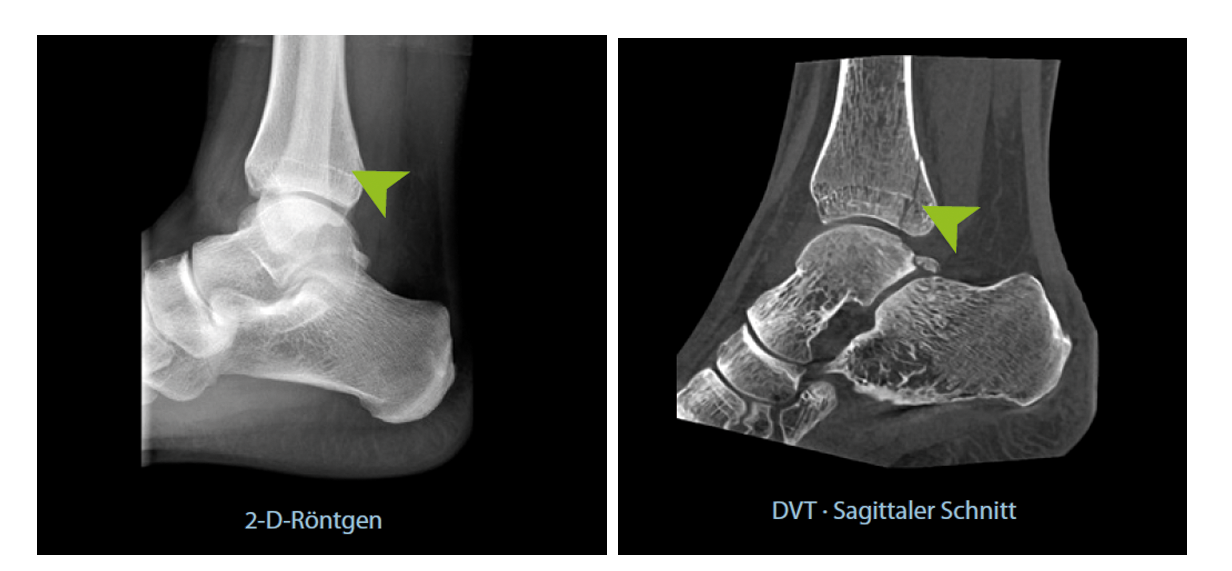

Um Sie als Patient zu schützen, ist der DVT mit Protokollen ausgestattet, die Aufnahmen mit einer besonders geringen Strahlenbelastung zulassen. Im Vergleich zu einer herkömmlichen CT hilft die DVT, die Strahlenbelastung um mindestens 50 % zu reduzieren. Damit liegt der Wert im Bereich der unvermeidlichen Strahlenbelastung, der man täglich ausgesetzt ist. Gleichzeitig liegt eine extrem hohe Bildqualität vor, die z.B. bei der Diagnostik von Brüchen eine deutlich höhere Sensitivität besitzt als ein normales Röntgenbild.

Die dreidimensionale Schnittbildgebung mit dem DVT bietet eine sehr hohe Bildqualität mit Schichtdicken von nur 0,2 mm (bei herkömmlichem CT / MRT meist 1-3 Millimeter). Dadurch können z.B. selbst kleinste Haarrisse bei Brüchen erkennbar werden, die in gängigen Verfahren übersehen werden könnten. Die hohe Auflösung kommt Ihnen als Patient zugute: Durch die klare und beeindruckende 3-D-Bildgebung lässt sich der Befund einfacher mit Ihnen besprechen und sorgt für eine bessere Nachvollziehbarkeit.